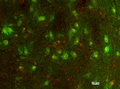

Our Anti-Tyrosine Hydroxylase (TH) mouse monoclonal primary antibody from Antibodies Incorporated is produced in-house from hybridoma clone LNC1. It detects chicken, frog, human, lizard, monkey, mouse, rat, vole, and zebrafish Tyrosine Hydroxylase (TH), and is ascites fluid. It is great for use in IHC, ICC, IP, WB.